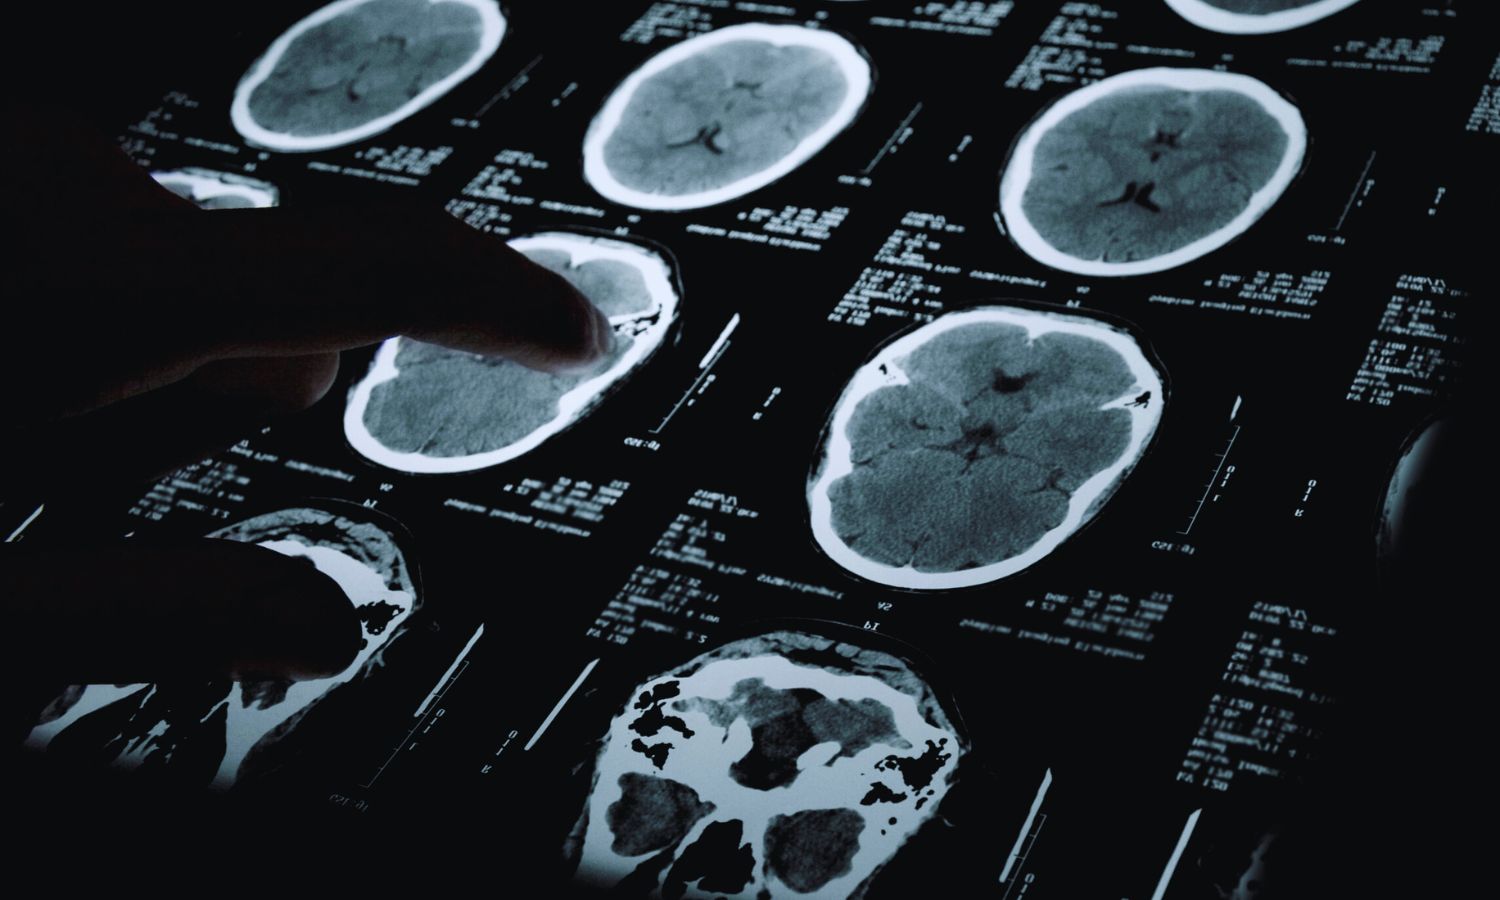

Por qué el cerebro convierte estímulos breves en emociones duraderas

Un estudio con humanos y ratones ha revelado que estímulos negativos breves pueden generar patrones emocionales prolongados en el cerebro. Se trata de un hallazgo clave para comprender trastornos como la depresión o el estrés postraumático.

No siempre entendemos nuestras emociones, pero no podríamos vivir con normalidad sin ellas. Guían nuestras decisiones y acciones. Sin embargo, cuando son inapropiadas o persisten demasiado, pueden volverse problemáticas. Pese a sus avances, la neurociencia y la psiquiatría aún comprenden poco sobre la actividad cerebral que da origen a las emociones, cómo nos impulsa y cómo puede enfermarnos.

Ahora, investigadores de Stanford Medicine (Estados Unidos) revelan en un estudio con humanos y ratones que estímulos negativos breves pueden generar patrones emocionales prolongados en el cerebro, lo que ayuda a comprender cómo se forman ciertos estados emocionales duraderos.

El trabajo, publicado en Science, forma parte del proyecto Circuitería Neural Humana de Stanford Medicine y ha descubierto, a través de mediciones cerebrales, que tras un estímulo desagradable breve —como puede ser una ráfaga de aire en el ojo—, el cerebro activa una segunda fase de actividad emocional que se prolonga más allá del estímulo inmediato.